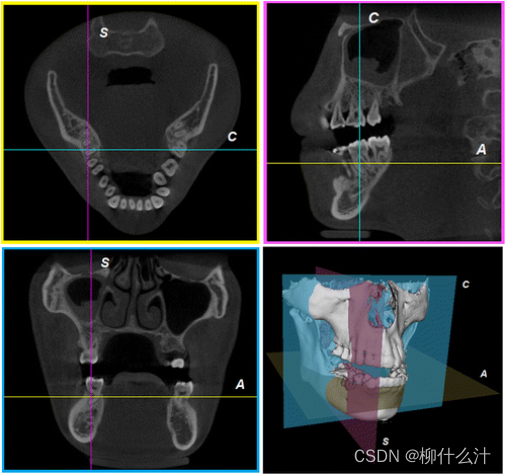

锥体束重建过程创造了一个三维矩阵,轴向平面(axial planes)从上到下的切片,矢状面(sagittal planes)是从左到右的切片,冠状面(coronal planes)是从前到后的切片。在多平面重建(MPR)窗口中,这三个正交的平面视图通过交叉线或十字线联系在一起,可以直接定位和导航。

倾斜和弯曲的重新格式化

创建体积图像之后,除了多平面格式化,斜向格式化允许用户以任何角度切开FOV(两个斜:重建三维图像时的不拘泥于水平而允许倾斜交叉多角度重建和做切片时的倾斜切片)。斜面改造的操作可以通过旋转图像本身或旋转交叉线来进行。由于斜面上的体素在水平或垂直方向上都不对齐,斜面改造需要插值。

第一张图是效果,第二章图是实现斜面改造的两种方法。